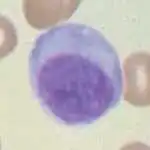

Imagen tomada con microscopio óptico de una célula plasmática teñida con hematoxilina-eosina. | ||

Las células plasmáticas son linfocitos grandes con una elevada proporción núcleo celular/ citoplasma y con un aspecto característico vistas al microscopio óptico. Tienen un citoplasma basófilo y un núcleo excéntrico con heterocromatina dispuesta en una característica forma de "rueda de carro". Su citoplasma también contiene una zona pálida que vista al microscopio electrónico contiene un extenso aparato de Golgi junto con los centriolos.[2] La abundancia de retículo endoplásmico rugoso combinada con un buen desarrollo del aparato de Golgi la hacen apta para la secreción de proteínas, en este caso inmunoglobulinas. El tipo de plasmocito descripto con estas características se denomina de tipo Marschalkó.